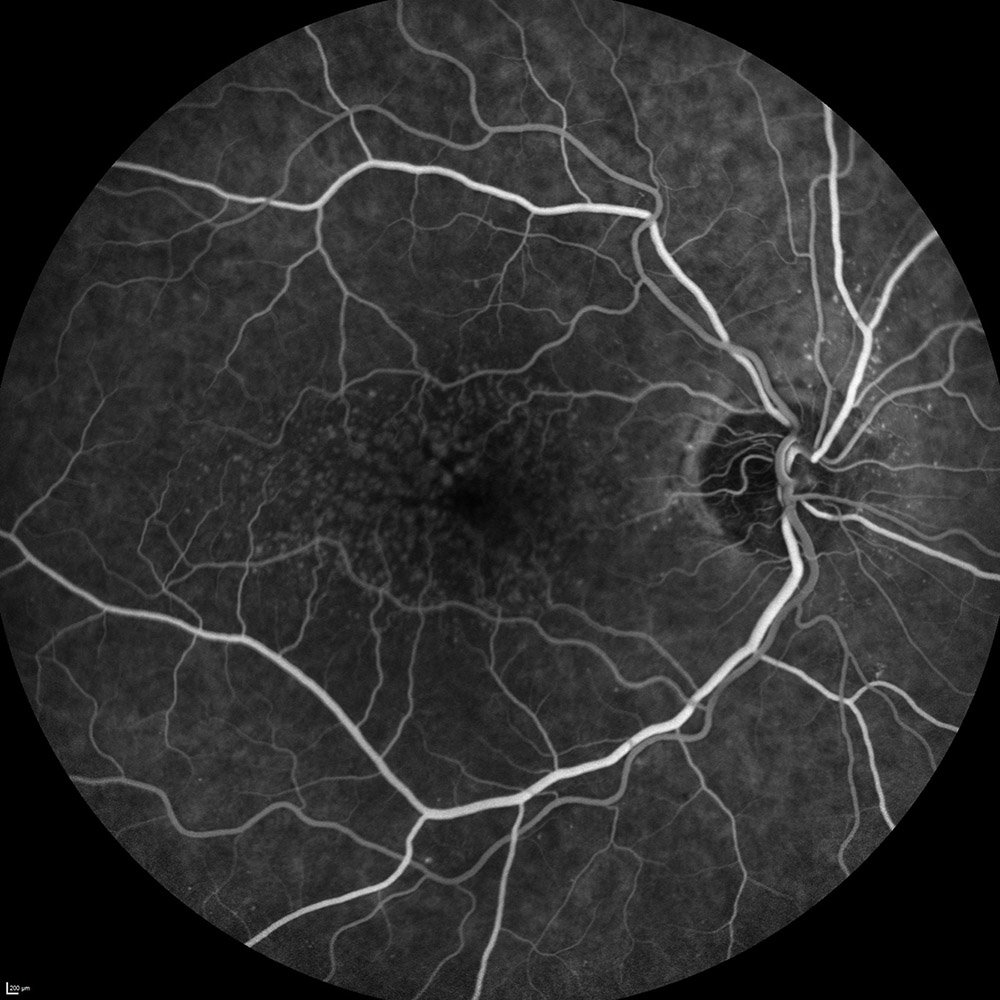

- L’angiographie

Une angiographie à la fluoréscéine ou au vert d’indocyanine (ICG) sera réalisée en cas de DMLA exsudative suspectée ou avérée. Cet examen consiste à photographier les vaisseaux de la rétine après injection intraveineuse d’un colorant fluorescent par voie veineuse pour mettre en exergue la présence de néovaisseaux.

Drusen typiques de la MLA

Néovaisseaux (occultes) typiques de la DMLA